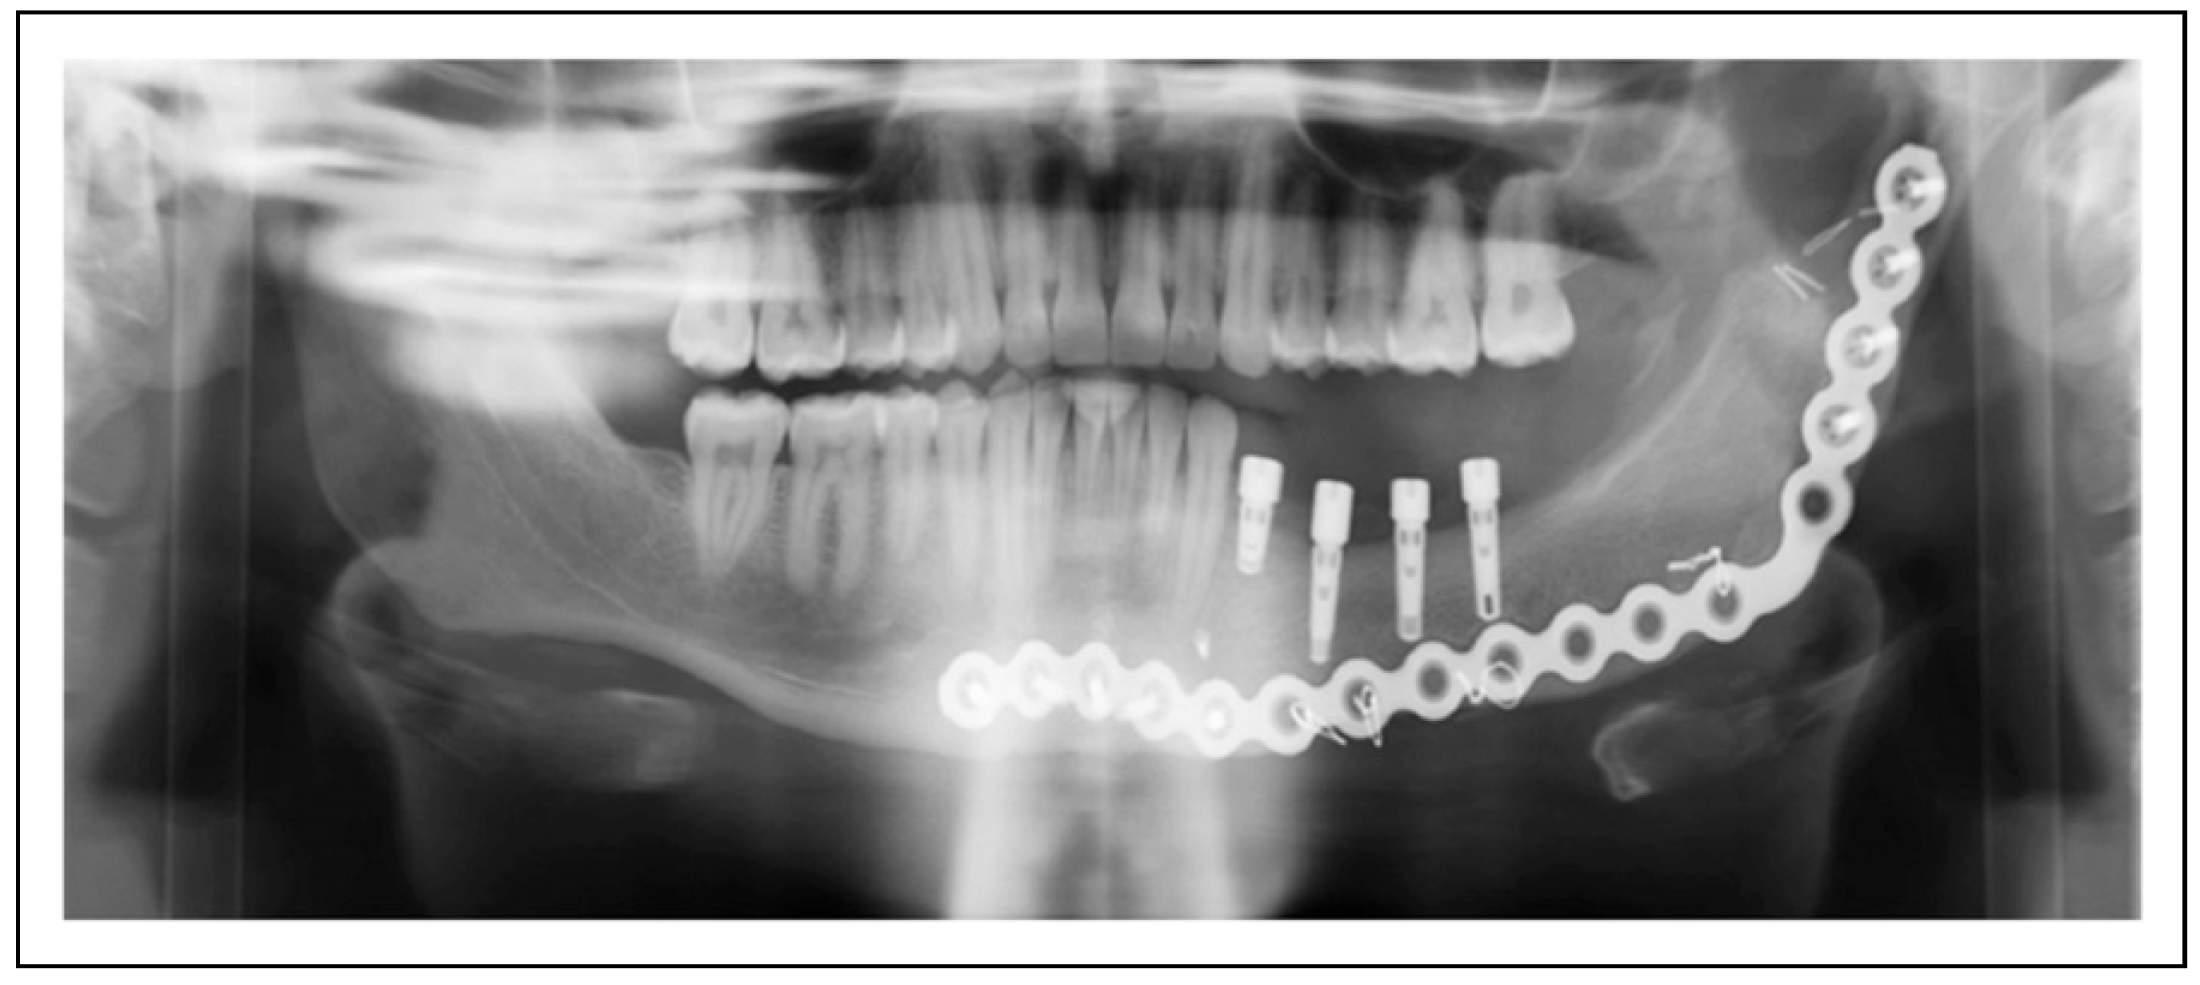

Figure 2.

Patient 12 is restored with 4 mandibular implants that support the dental prosthesis. The implants remain stable and without pathology after 12 months.